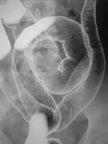

X線TV検査

Ⅹ線TV装置は、身体の動きや状態を透視像でリアルタイムに見ながら、最適な画像を撮影する装置です。主な検査としては、消化管造影検査、骨折などを整復するための整形外科的検査、内視鏡を併用する検査です。

当院のⅩ線TV装置は、FPD(フラットパネルディテクタ)を搭載しているものもあり、従来の装置と比べ低線量での検査が可能で、より質の高い画像を提供しています。